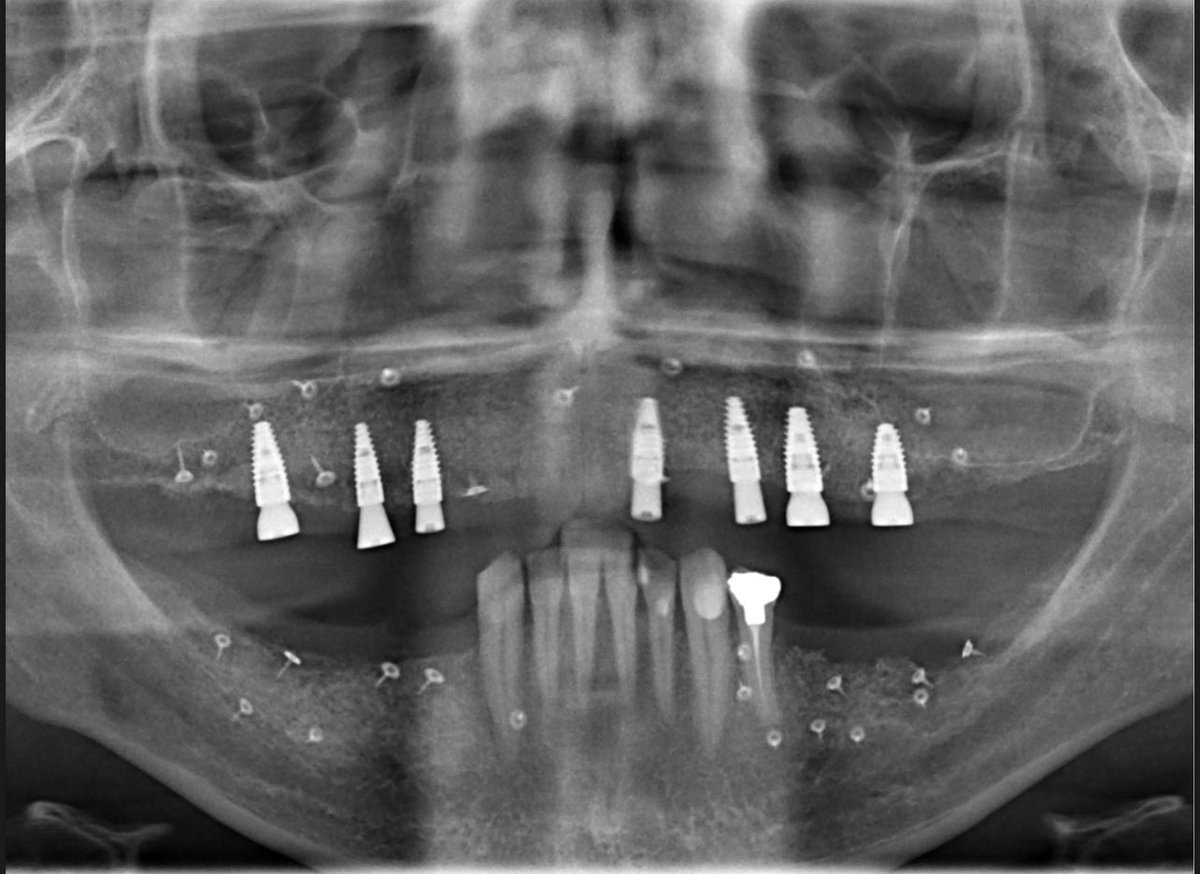

من مراحل اعادة تأهيل كامل للفكين عن طريق الزراعه.. تم فيها علاج بروز الاسنان واعادة الاطباق الوظيفي والجمالي للمراجع بالتعاون مع د.مشاري المطيري مشاري بدر بن زريبان في قسم التركيبات الثابتة والمتحركه #زراعة_الاسنان #التركيبات_الثابته #التركيبات_المتحركه

حالة إعادة تأهيل كامل للفكين لمراجعي عن طريق زراعة العظم والاسنان والتركيبات.. الجزء الجراحي مع المعماري الكبير د.ياسر د.ياسر الزهراني 😍 وكل الشكر للمراجع على تحمله خطتي العلاجيه ورحلة العلاج المطوّلة🌹